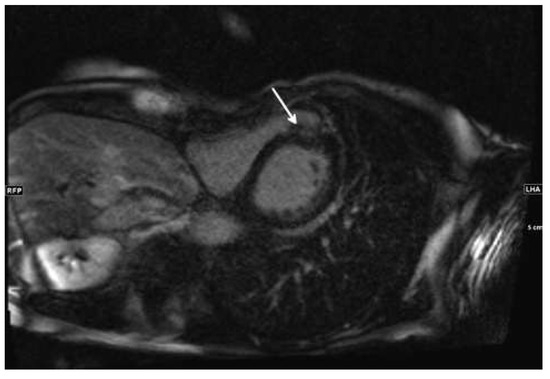

Left Ventricular Apical Ballooning Syndrome with Extensive Myocardial Late Gadolinium Enhancement: Tako-Tsubo Cardiomyopathy, Perhaps Not as Benign as Previously Thought?

by Vincent Gabus, Juerg Schwitter, Eric Eeckhout and Didier Locca

Cardiovasc. Med. 2012, 15(11), 325; https://doi.org/10.4414/cvm.2012.00120 - 21 Nov 2012

Viewed by 148

Abstract

Aim: In patients meeting the criteria for LV apical ballooning syndrome, CMR typically identifies myocardial oedema without Late Gadolinium Enhancement (LGE). However, LGE does not exclude LV apical ballooning syndrome and small necrotic areas can be seen in the acute setting resolving [...] Read more.

Aim: In patients meeting the criteria for LV apical ballooning syndrome, CMR typically identifies myocardial oedema without Late Gadolinium Enhancement (LGE). However, LGE does not exclude LV apical ballooning syndrome and small necrotic areas can be seen in the acute setting resolving at follow-up. Results: We describe the case of a 61 year-old woman admitted with a 2 h history of retrosternal chest pain. ECG demonstrated Q waves and dynamic ST segment elevation. Cardiac enzymes on admission were elevated. Coronary angiography showed unobstructed coronary arteries. Left ventriculography showed apical ballooning. Cardiac Magnetic Resonance (CMR) revealed antero-septal and anterior akinesia. Myocardial oedema was seen in the septal wall. Late gadolinium enhancement (LGE) was seen in the same territory indicating the presence of necrosis. A follow up CMR scan was performed at 3 months showing a complete resolution of the septal oedema. However, on LGE sequences there was evidence of persistent extensive fibrotic scar located in the septal wall. The size of this fibrotic scar was 20% bigger than on the previous scan. Conclusions: Detection and quantification of a scar is important, as scar tissue on LGE images has been described as a predictor of major adverse cardiac events. Therefore, this case suggests that the spectrum of Tako-tsubo cardiomyopathy may include a more severe variant than previously described. CMR examinations could serve as a useful means to identify severe cases and predict potential complications of this pathology as well as to drive therapeutic decisions. Full article

Show Figures

Figure 1